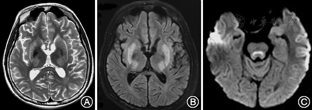

患者男性,16岁,因"阵发性木讷,四肢僵硬、构音障碍10个月"于2016年8月29日入院。患者于10个月前无明显诱因出现阵发性木讷,目光呆滞,持续数十秒后自行好转,而后出现上肢不自主抖动,呈持续性,逐渐出现双上肢先后僵硬,呈屈曲状,不能伸直,后双下肢僵硬,行走不稳。构音障碍,言语不能,饮水呛咳,症状呈进行性加重,自起病来,无发热、头痛,无晕倒、口吐白沫,无肢体偏瘫,无大小便失禁。既往史家族史无特殊。神经系统体检:意识清楚,认知功能尚可,言语不能;K-F环(+);四肢肌张力高,双上肢肌力Ⅳ级,双下肢肌力Ⅴ级,四肢腱反射(+),病理征阴性。生化检查:尿铜792.28 μg /24 h(正常值15~30 μg/24 h);血清铜蓝蛋白测定0.12 g/L (正常值0.2~0.6 g/L);尿常规:隐血3+,蛋白质(±),红细胞832.92个/μl[正常值0~5个/μl];血常规:白细胞计数3.51×109/L[正常值(4~10)×109/L],红细胞计数4.08×1012/L[正常值(4.09~5.74)×1012/L],血红蛋白123 g/L(正常值131~172 g/L),血小板计数78×109/L[正常值(85~303) ×109/L]。凝血四项:纤维蛋白原浓度1.43 g/L(正常值2~4 g/L),凝血酶原时间14.6 s (正常值9~13 s ),国际标准比率1.25 (正常值0.8~1.2),凝血酶原活动度60.1% (正常值70%~150%)。肝功能:碱性磷酸酶210.53 U/L(正常值34~104 U/L),谷氨酰转酞酶58.97 IU/L(正常值5~55 IU/L),纤维结合蛋白127.03 mg/L(正常值180~280 mg/L)。粪便常规+潜血、肾功能、电解质、肌酶谱、C反应蛋白、红细胞沉降率、血脂、餐后2 h血清葡萄糖、叶酸、维生素B12、游离甲状腺素测定等未见异常。患者心电图示窦性心律,大致正常心电图。脑电图:间歇期,左额区见较多中波慢波及尖波,尖慢波;诊断提示:间歇期,痫样放电及慢波,脑区性,左额著。上腹部CT提示肝硬化、脾肿大。颅脑磁共振平扫:双侧额、顶、颞叶脑沟变窄,脑组织肿胀,呈稍长T1稍长T2信号(图1A),DWI呈脑回样高信号(图1B),双侧豆状核、丘脑及外囊、胼胝体、脑干背侧呈片状稍长T1、稍长T2信号,双侧苍白球及小脑齿状核呈等T1、短T2信号(图2)。颅脑增强扫描:双侧额顶叶脑回线样明显强化(图1C)。

本文HLD患者颅脑MRI表现为相对非典型的双侧额、顶、颞叶脑沟变窄,脑组织肿胀,呈稍长T1稍长T2信号,弥散加权成像呈脑回样高信号,增强提示双侧额顶叶脑回线样明显强化以及HLD典型的表现如双侧豆状核、丘脑及外囊、胼胝体、脑干背侧呈片状稍长T1稍长T2信号。脑回线样强化与血脑屏障破坏有关,且脑实质表面强化通常系血管性疾病或炎症性疾病所致[7]。患者有HLD罕见的癫痫发作[8],癫痫所致血管舒张也可导致脑回线样强化。结合国外1例额叶脑回线样强化伴有癫痫发作的HLD患者在抗癫痫治疗1个月后,癫痫症状和脑回线样强化消失,然而额叶皮质下白质影像学改变仍存在且范围相对更大[9],可以推测脑回线样强化与癫痫发作相关,可能是癫痫发作导致脑回线样强化,加剧了脑白质病变。相关研究还发现[8],HLD患者中有癫痫发作者比无发作者有更多的脑白质病变,特别是额叶皮质下病变与癫痫发作呈显著相关。且提示未干预控制的HLD患者癫痫发作,MRI上可能出现脑白质空泡。癫痫发作不是HLD患者常见表现,其往往合并有广泛白质病变[10,11]。目前癫痫与皮质下白质损害因果关系暂不明确。由于HLD影像学存在多样性,诊断应该拓宽思路,还需结合临床病史,及其余辅助检查。